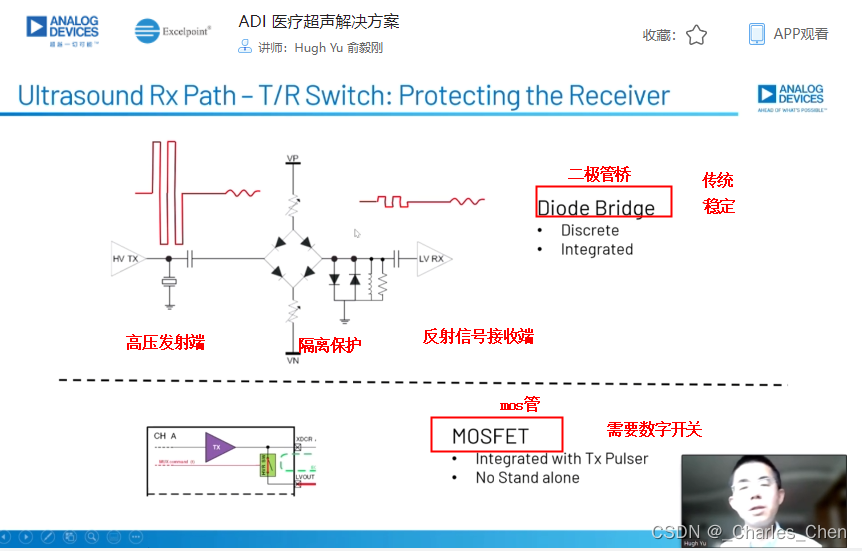

Tx/Rx开关

Tx/Rx开关可以保护低噪声放大器免受高压发射脉冲的影响,同时在接收间歇期间隔离低噪声放大器输入和发射机。该开关一般采用一组正确偏置的二极管阵列实现,当有高压发射脉冲出现时,它们会自动闭合或断开。Tx/Rx开关必须具备很快的恢复时间,以保证接收机在发射一个脉冲后能够立刻开启。这些快速恢复时间对于浅埋成像和提供低导通电阻确保接收灵敏度至关重要。